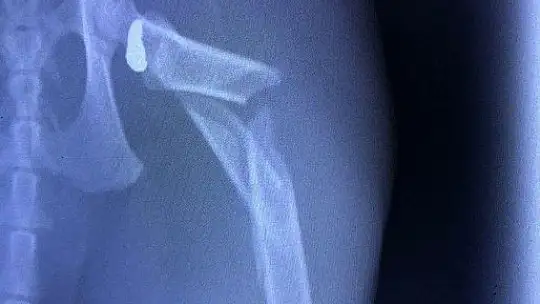

Muğla'nın Datça İlçesinde Defne Bardakçı'ya ait Köpük isimli kedi eve kanlar içinde geldi. Havalı tüfekle vurulduğu anlaşılan kedi Gökova Hayvan Hastanesinde ameliyata alındı.

Kedinin sahibi Defne Bardakçı, "Kedimizin vurulduğunu fark edince hemen veterinere götürdük. Ameliyat için bizi Gökova Hayvan Hastanesine yönlendirdiler. Vücudunda 6 kırık tespit edildi. Hayvan hastanesinde gerçekleştirilen ameliyatla saçma çıkarıldı. Sokağa çıkma yasağında kedimiz dışarıda geziyordu. Datça gibi hayvansever bir ilçede böyle bir şey yaşamak bizi hem şaşırttı, hem de üzdü. Havalı tüfekle vurulduğu için sesi duymadık. Kedimiz eve yaralı halde kanlar içinde gelince şoke olduk" dedi.